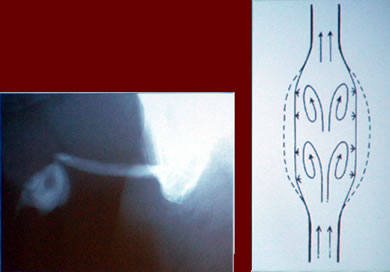

"Новые технологии в лечении стриктур уретры"